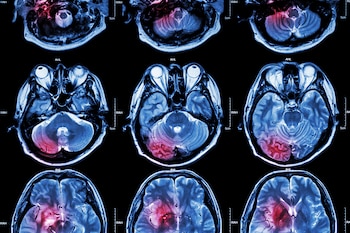

Entre 120.000 y 150.000 personas sufren de Parkinson en España, con 10.000 casos nuevos al año. Según la Sociedad Española de Neurología (SEN), el número de pacientes se duplicará en 20 años y se triplicará en 2050. Por ello, buena parte de las investigaciones actuales de la ciencia giran en torno a esta enfermedad neurodegenerativa.

Un equipo de científicos de la Facultad de Medicina de la Universidad de Yale (Estados Unidos) ha logrado identificar dos proteínas clave que podrían ser las responsables de la progresión del Parkinson. Localizadas en las neuronas motoras, han sido señaladas como responsables del transporte de la proteína mal plegada alfa-sinucleína, un elemento cuya acumulación desencadena la muerte neuronal característica de la enfermedad.

La enfermedad de Parkinson se caracteriza por una degradación paulatina de las neuronas cerebrales, fenómeno en el que la acumulación y propagación de la alfa-sinucleína resulta determinante. Aunque se tiene constancia de que esta proteína avanza de una célula a otra, hasta ahora los mecanismos precisos que facilitan dicho desplazamiento se desconocían. El equipo dirigido por Stephen Strittmatter, profesor de Neurología y responsable del Departamento de Neurociencias en Yale School of Medicine, ha presentado ahora datos que apuntan a los transportadores mGluR4 y NPDC1 como actores cruciales en este proceso.